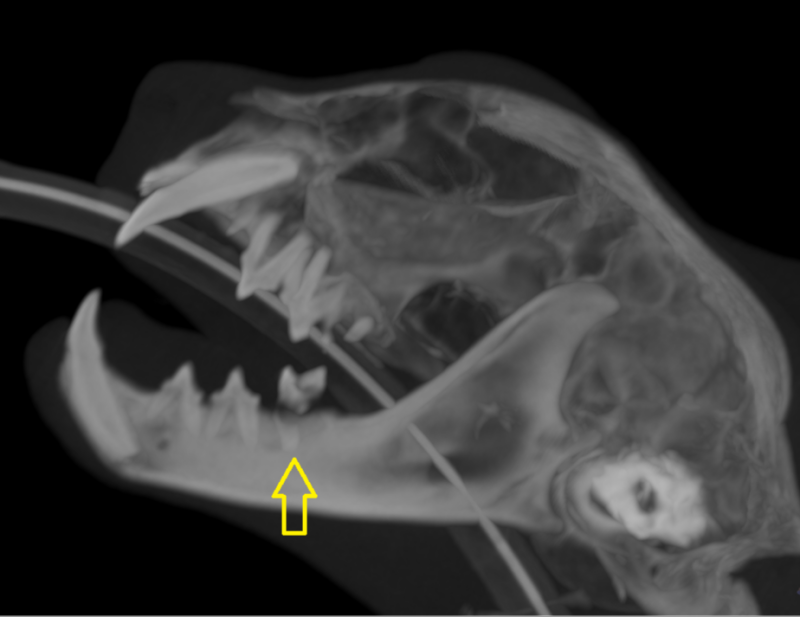

Voorbeelden van verdoken tand problemen . Op radiografie zie je wat zich onder het tandvlees afspeelt.